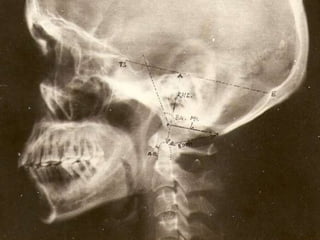

CRANIOMETRY

• Craniometry -series of lines, planes & angles to define the normal

anatomic relationships of the CVJ.

• These measurements can be taken on plain X rays, 3D CT or on MRI.

• No single measurement is helpful.

• Disadvantage --anatomic structures and planes vary within a normal

Lines,angles radiologic diagnosis of C.V

anomalies.

Chamberlain’s line

• From tip of hard palate to posterior tip of Foramen Magnum

(opisthion).

• It helps to recognise basilar invagination which is said to be present if

the tip of the dens is >3 mm above this line

Mc Gregor’s line (basal line)

• Line drawn from posterior tip

of Hard palate to lowest part

of Occiput

• Odontoid tip >5mm above =

Basilar Invagination

• Position changed with flexion

and extension so not used.

• Should be used when lowest

part of occipital bone is not

Foramen Magnum

Wackenheim’s clivus canal line

• Line drawn along

clivus into cervical

spinal canal

• Odontoid is ventral

and tangential to

this line

• If not –suggest AAD

or BI

Welcher’s Basal Angle

• Nasion to tuberculum sella

• Tuberculum sellae to the basion along plane of the clivus

• Normal – 124- 142

• > 140- platybasia

• < 130 is seen in achondroplasia

Boogard ‘s Angle

• 1st line between

Dorsum sellae to

Basion & McRae’s

line.

• Average - 122

• > 135,Basillar

impression

Bulls angle

• Line representing

prolongation of hard palate

and line joining the

midpoints of the ant & post

arches of C1.

• Normal : <10

• Basilar invagination ->13